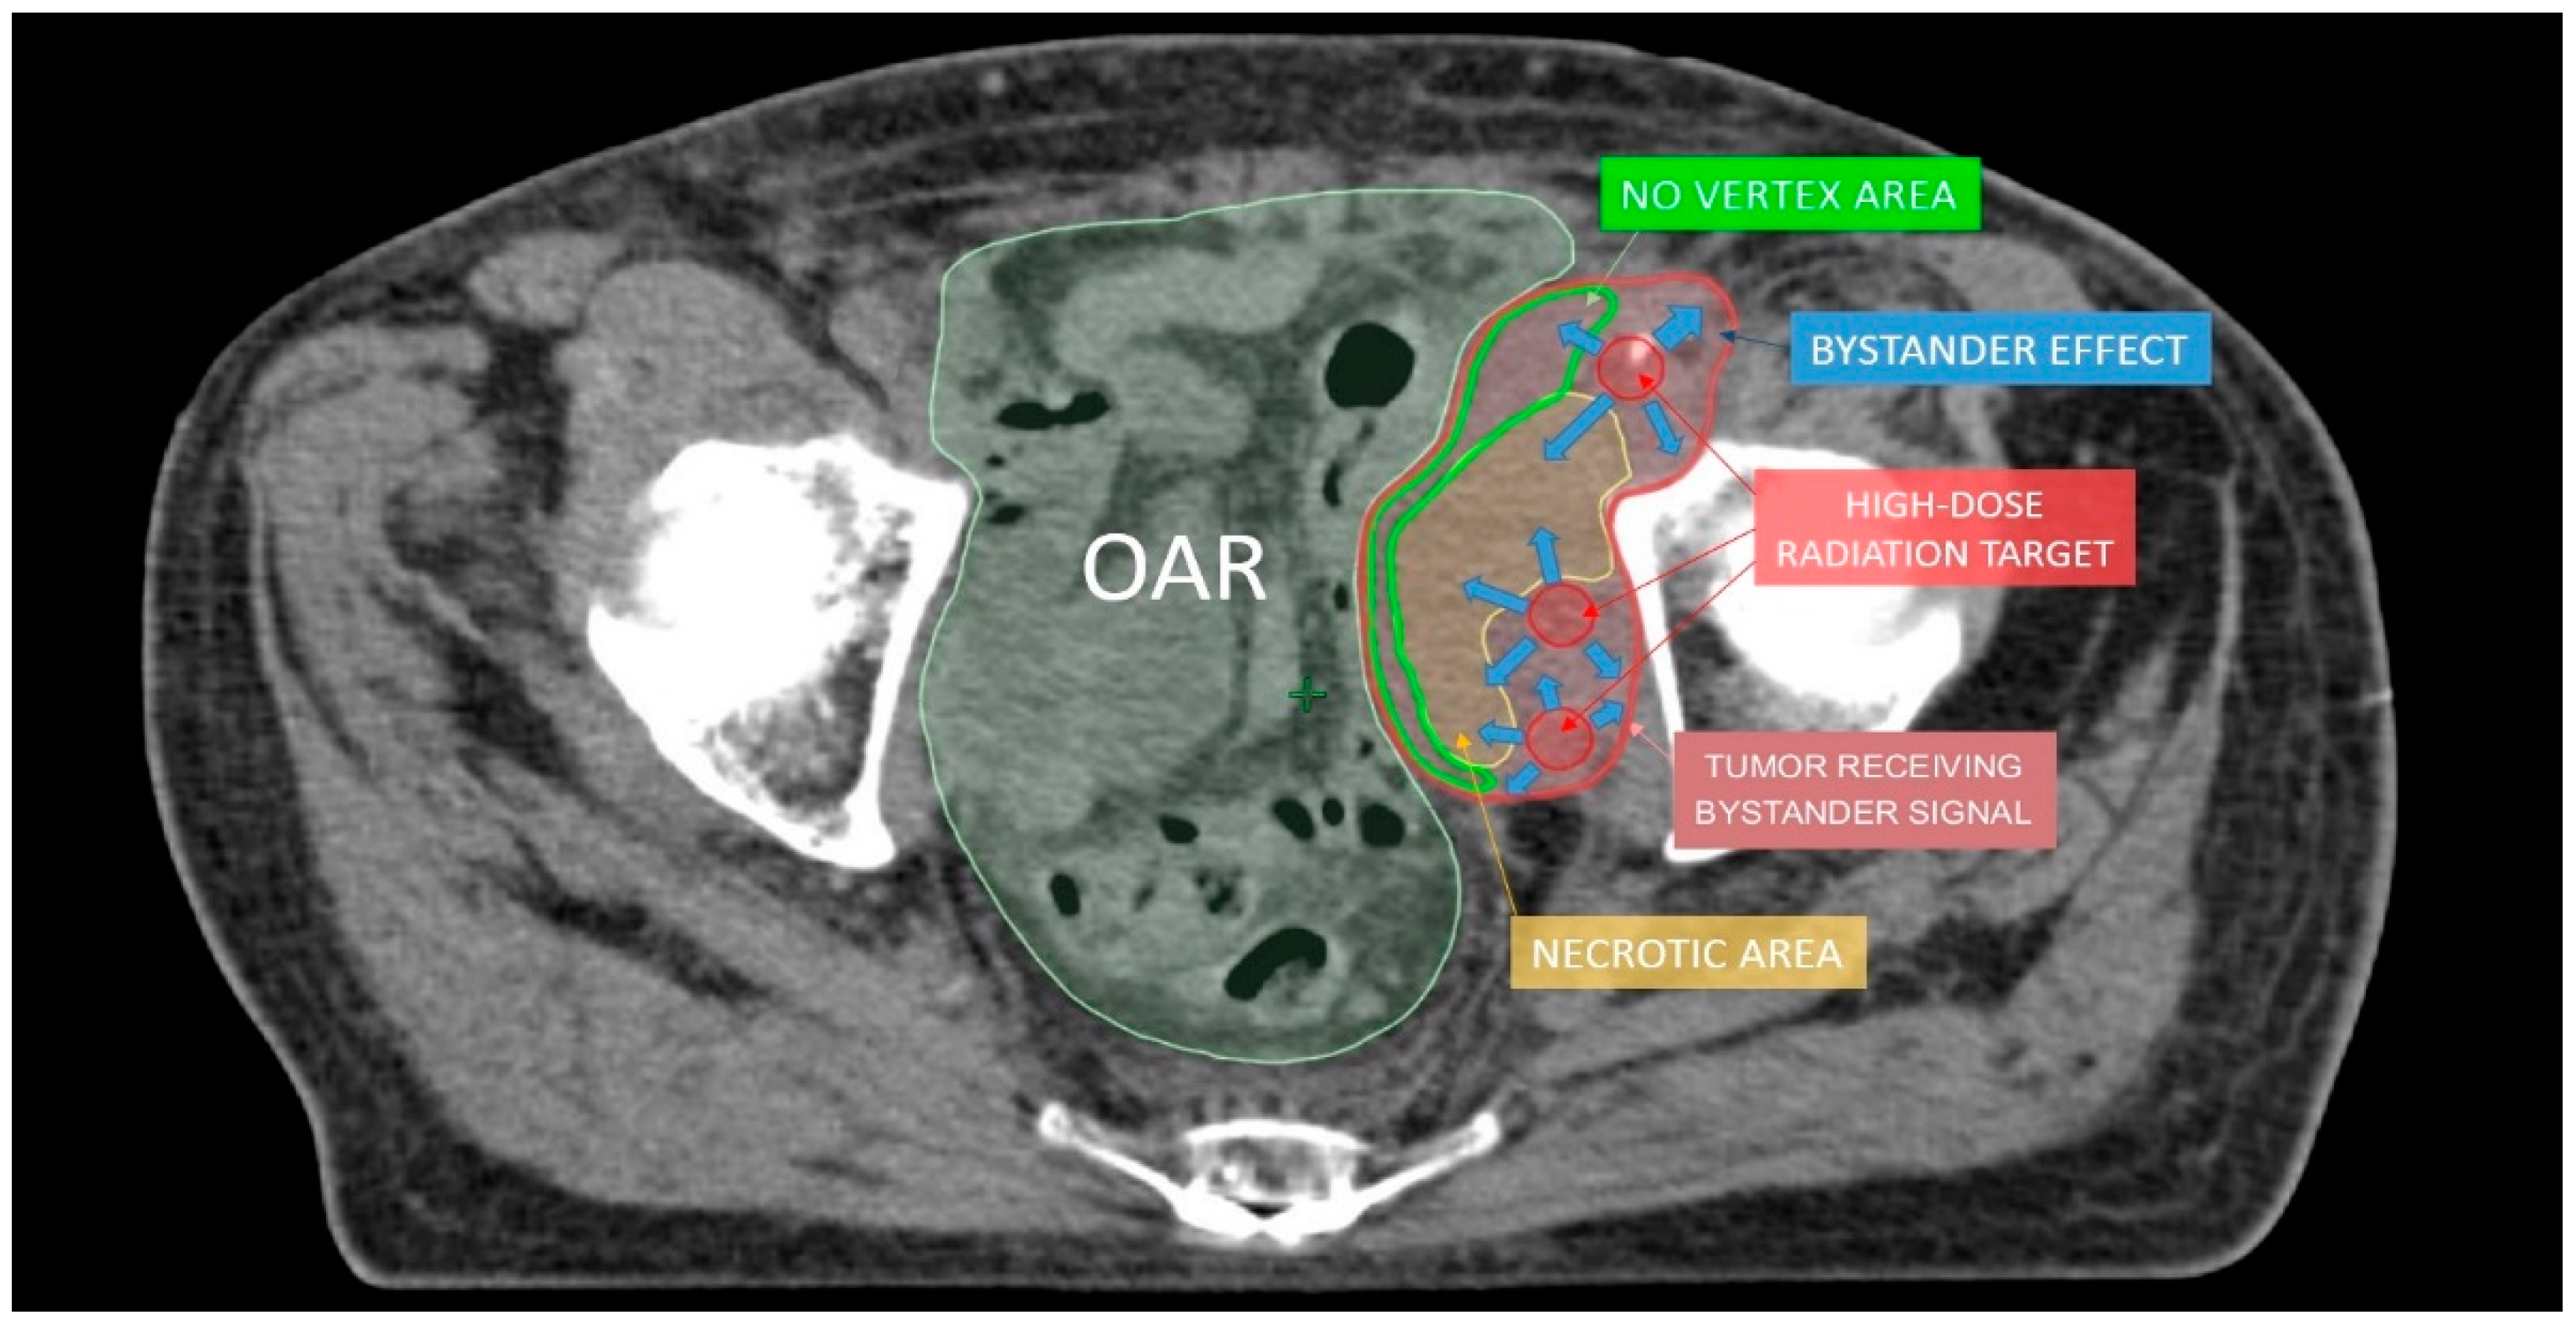

2. Lattice Radiotherapy: Concept

4. Oxygen-Guided Radiotherapy: Oxygen Is the Needed Comburent for Radiotherapy, Not Only for Fire

5. OGRT in Clinical Practice

7. A Look to the Future and Open Questions

- Asur, R.; Butterworth, K.T.; Penagaricano, J.A.; Prise, K.M.; Grifn, R.J. High dose bystander efects in spatially fractionated radia-tion therapy. Cancer Lett. 2015, 356, 52–57. [Google Scholar] [CrossRef] [Green Version]

- Yan, W.; Khan, M.K.; Wu, X.; Simone, C.B.; Fan, J.; Gressen, E.; Zhang, X.; Limoli, C.L.; Bahig, H.; Tubin, S.; et al. Spatially fractionated radiation therapy: History, present and the future. Clin. Transl. Radiat. Oncol. 2020, 20, 30–38. [Google Scholar] [CrossRef] [Green Version]

- Tubin, S.; Khan, M.K.; Salerno, G.; Mourad, W.F.; Yan, W.; Jeremic, B.; Tubin, S. Mono-institutional phase 2 study of innovative Stereotactic Body RadioTherapy targeting PArtial Tumor HYpoxic (SBRT-PATHY) clonogenic cells in unresectable bulky non-small cell lung cancer: Profound non-targeted effects by sparing peri-tumoral immune microenvironment. Radiat. Oncol. 2019, 14, 1–11. [Google Scholar] [CrossRef] [Green Version]

- De Olza, M.O.; Bourhis, J.; Irving, M.; Coukos, G.; Herrera, F.G. High versus low dose irradiation for tumor immune reprogramming. Curr. Opin. Biotechnol. 2020, 65, 268–283. [Google Scholar] [CrossRef] [PubMed]

- Menon, H.; Chen, D.; Ramapriyan, R.; Verma, V.; Barsoumian, H.B.; Cushman, T.R.; Younes, A.; Cortez, M.A.; Erasmus, J.J.; De Groot, P.; et al. Influence of low-dose radiation on abscopal responses in patients receiving high-dose radiation and immunotherapy. J. Immunother. Cancer 2019, 7, 237. [Google Scholar] [CrossRef] [Green Version]

- Barsoumian, H.B.; Ramapriyan, R.; I Younes, A.; Caetano, M.S.; Menon, H.; I Comeaux, N.; Cushman, T.R.; E Schoenhals, J.; Cadena, A.P.; Reilly, T.P.; et al. Low-dose radiation treatment enhances systemic antitumor immune responses by overcoming the inhibitory stroma. J. Immunother. Cancer 2020, 8, e000537. [Google Scholar] [CrossRef]